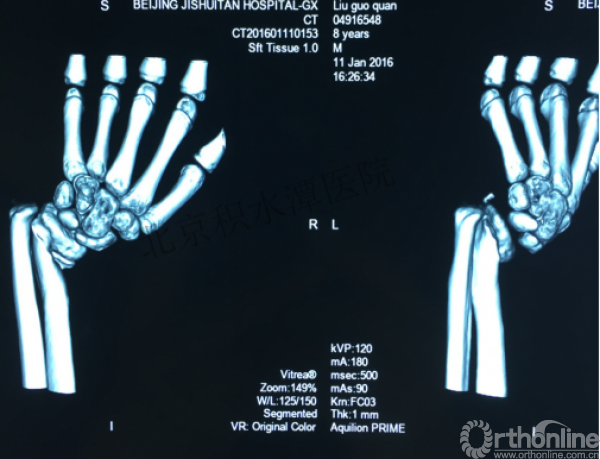

病例分享四

女孩、8岁,桡骨远端骨折

原始损伤

伤后1个月

伤后14个月